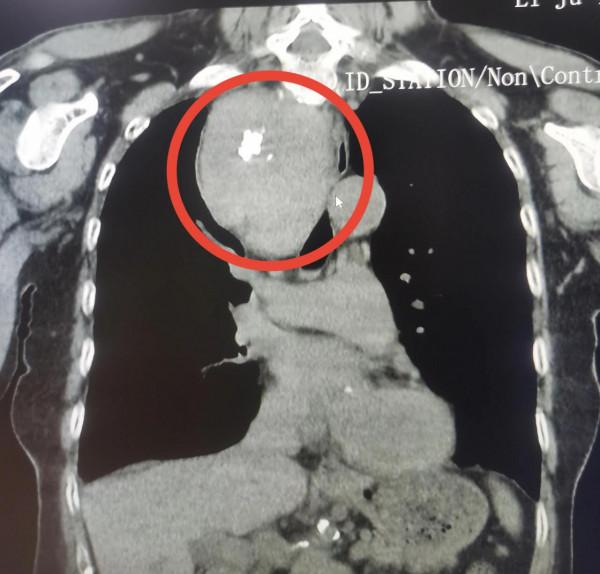

近日,劉婆婆因為肋骨不適到武漢市中心醫院後湖院區做檢查,卻意外被發現其胸腔上部分有一個拳頭大小的腫物。該院後湖院區胸外科與甲乳外科專家根據劉婆婆的相關檢查結果,考慮其胸腔內的腫物為甲狀腺腫瘤,應是其頸部的腫瘤長進了胸腔。由於腫瘤壓迫了附近的氣道,所以劉婆婆會經常出現胸悶氣短的情況。

隨後,兩科室專家團隊為劉婆婆完成了相關的術前檢查,為其進行了胸骨後甲狀腺病損切除術,順利摘掉了這個拳頭大小壓迫劉婆婆氣到的腫瘤。經過後續的對症支援治療,劉婆婆恢復迅速,於25日出院。